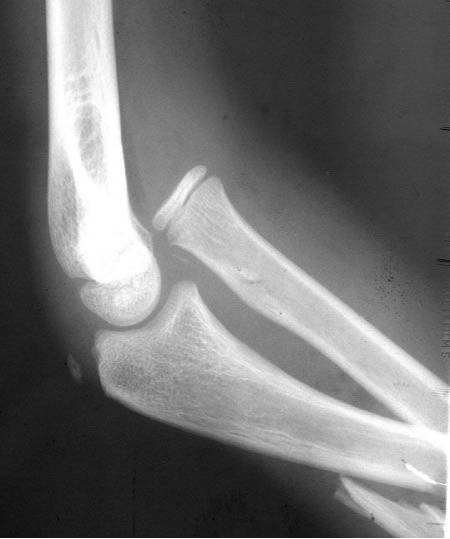

38种特殊骨折经典影像,你见过多少?

干货|这38种特殊骨折经典影像,建议收藏!

肱骨髁上骨折